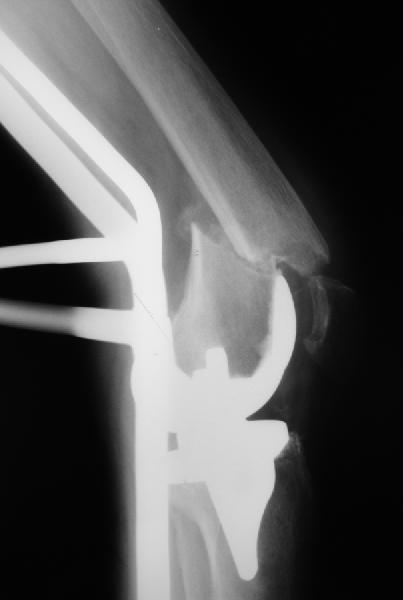

Александр Николаевич, сколько у вас таких клиентов? Каковы исходы? Только ли ЦИТОвские стержни использовали? Были ли с неправильно сросшимися переломами? У меня есть 2 клиента. Только переломы срослись у одного с вальгусом у другого с варусом. Планирую ту же схему через остеотомию.

Были ли с неправильно сросшимися переломами? У меня есть 2 клиента. Только переломы срослись у одного с вальгусом у другого

Были пока только переломы и несращения. С деформациями как-то не попадались пока.